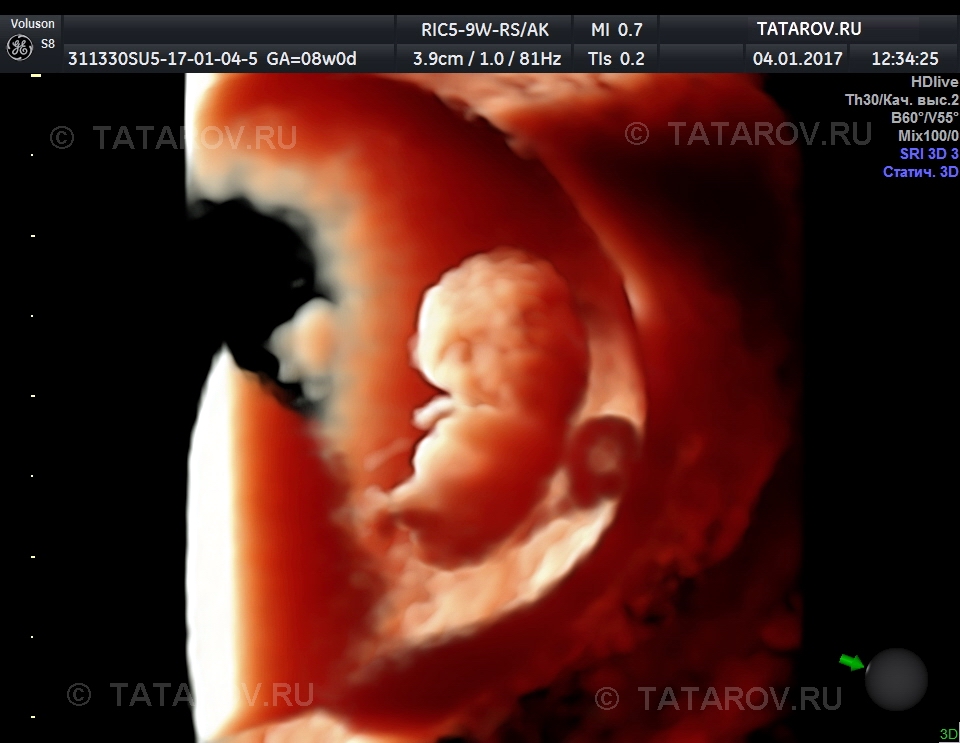

Развитие эмбриона на 8 неделе беременности